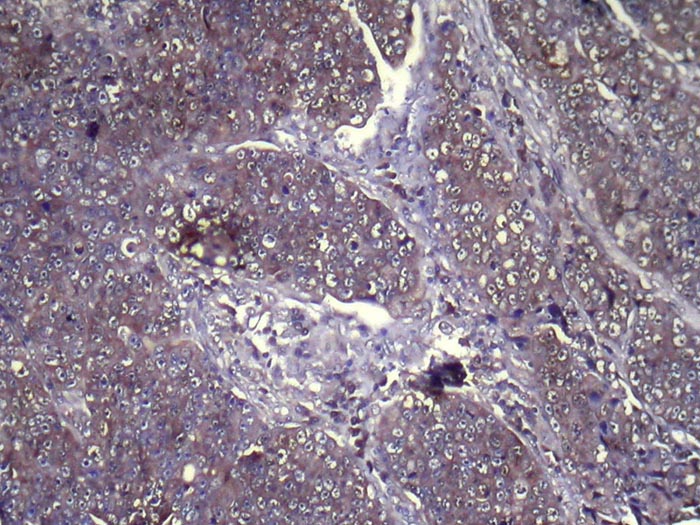

Immunohistochemical analysis of paraffin-embedded Human Breast cancer tissue using #42994 at dilution 1/100,

Immunohistochemistry: 1:100-1:200